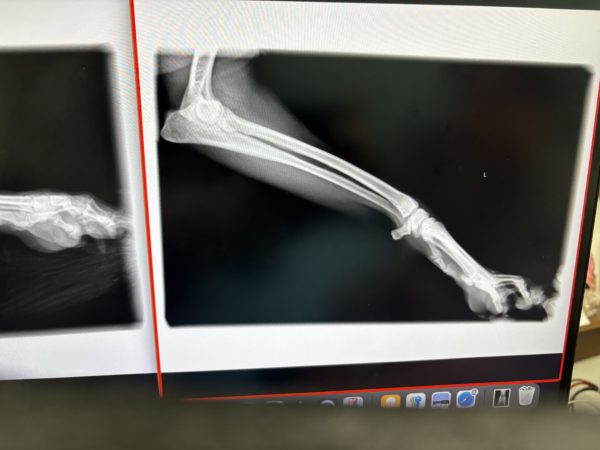

私には何がどうだか全く分からない画像ですが

骨折もヒビすら見受けられないとのことでホッ😌

靭帯やひどい捻挫ならレントゲンにも映ることがあるそうですが

それも見受けられないとのことで